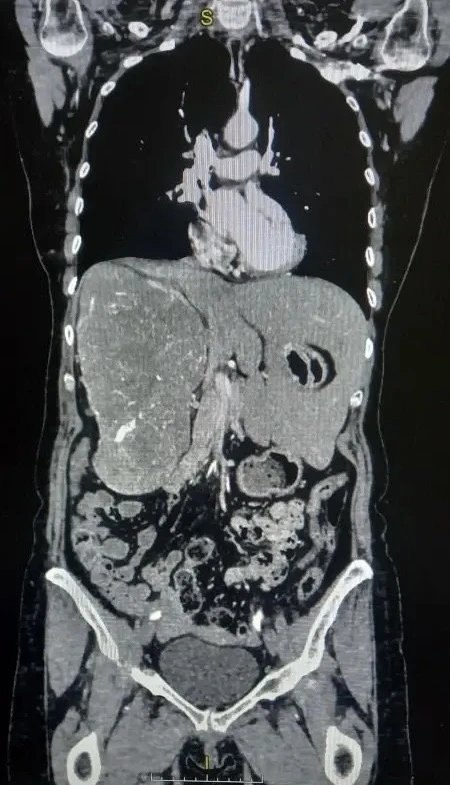

Хирурги Волгоградского областного онкологического диспансера провели редкую операцию на почке у пациентки с гигантской опухолью, сместившей печень из правой стороны живота в левую.

Опухоль размером 16,5х11,5х21,1 см почти полностью заняла правую половину брюшной полости, а правая почка почти не функционировала. В феврале 2026 года была выполнена радикальная нефрэктомия, операцию провел врач Проноза В.В. Все прошло без осложнений, контрольное УЗИ подтвердило успешность операции. Пациентка выписана через 8 дней.

Фото: Комитет здравоохранения Волгоградской области